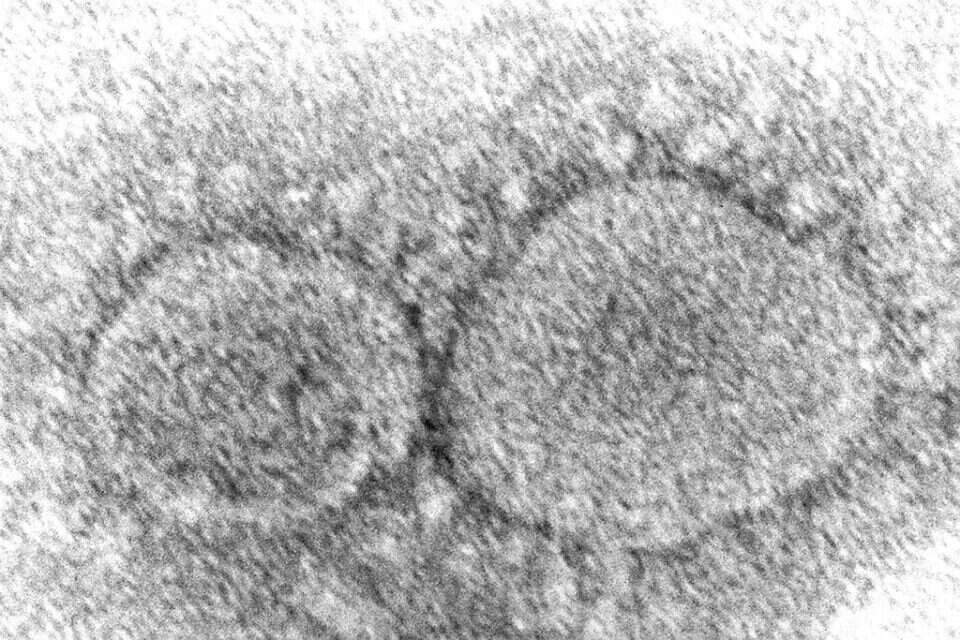

צילום מיקרוסקופ של נגיף הקורונה, צילום: איי.פי

וריאנט חדש של נגיף הקורונה אותר על ידי חוקרים בדרום צרפת, לאחר ש-12 מקרים שלו נתגלו בקרב נוסעים ששבו למדינה מקמרון שבמערב אפריקה.